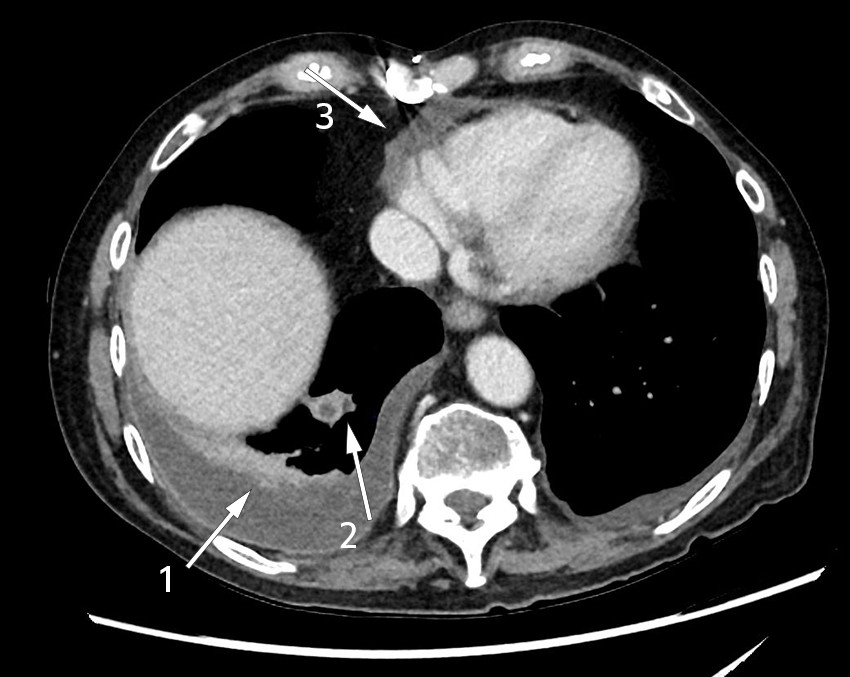

Tre dager etter innleggelsen klaget pasienten over snøvlete tale, og man konstaterte dysartri. CT og MR caput påviste abscessuspekte lesjoner i høyre temporallapp og cerebellarhemisfære (figur 2). Det var ingen vekst i fire sett blodkulturer. I henhold til norske og internasjonale retningslinjer for behandling av hjerneabscesser ble cefotaksimdosen økt til 4 g × 3 og metronidazol 1,5 g × 1 intravenøst lagt til. For å avdekke en eventuell emboluskilde ble det utført transtorakal og transøsofageal ekkokardiografi, som ikke viste holdepunkt for endokarditt. På grunn av forverret dysartri ble det fire dager senere tatt ny MR caput, som viste økende størrelse på begge hjerneabscessene. Påfølgende dag ble det utført abscessdrenasje av nevrokirurg i diagnostisk og terapeutisk øyemed, med evakuering av brunlig puss. Materialet ble sendt til histologisk undersøkelse og dyrkning for å detektere bakterier og sopp. Ved mikroskopi av gramfarget preparat ble det ikke påvist bakterier. Prøvematerialet ble også sendt til 16 S rDNA-sekvensering.

Abscesser i sentralnervesystemet oppstår i 50 % av tilfellene som følge av direkte spredning fra nærliggende fokus og i 30 % som ledd i hematogen spredning, mens det i 20 % av tilfellene er ukjent spredningsmønster (6). Ved abscessdiameter større enn 2,5 cm anbefales drenering (7). Abscesser sekundært til lokale fokus har ofte polybakteriell etiologi med munnhule- eller luftveismikrober (8), mens abscesser som følge av hematogen spredning typisk er monobakterielle (6). Som primærdiagnostisk verktøy ved mistanke om intracerebral patologi er CT godt egnet, mens kontrastforsterket MR er nødvendig for å differensiere abscess fra annen patologi. Diagnostisk aspirasjon og biopsi av abscessinnhold bør planlegges i samråd med infeksjonslege, nevrokirurg og mikrobiolog for å sikre riktig og rask håndtering av prøvematerialet. Prøvematerialet til mikrobiologisk diagnostikk skal tas på sterilt glass til mikroskopi, både til Gram- og Ziehl-Neelsen-farging, anaerob og aerob dyrkning samt dyrkning av mykobakterier. Hvis mulig ønskes også prøvemateriale på blodkulturmedium. Lumbalpunksjon har liten nytteverdi ved abscesser i sentralnervesystemet og er forbundet med fare for herniering.